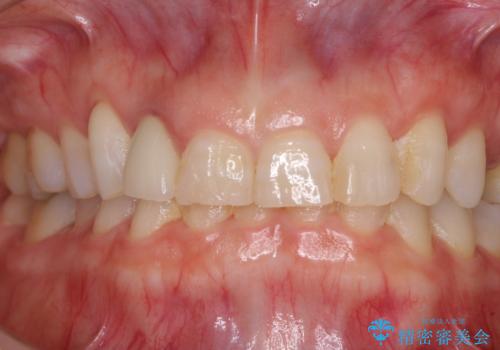

- 前歯のクラウン周りに歯肉が腫れていることを気にして来院された患者様です。

元々磨き残しによる歯肉の腫脹がありましたが、クラウンが歯肉深くに装着されていたため、特に腫脹が目立っていました。